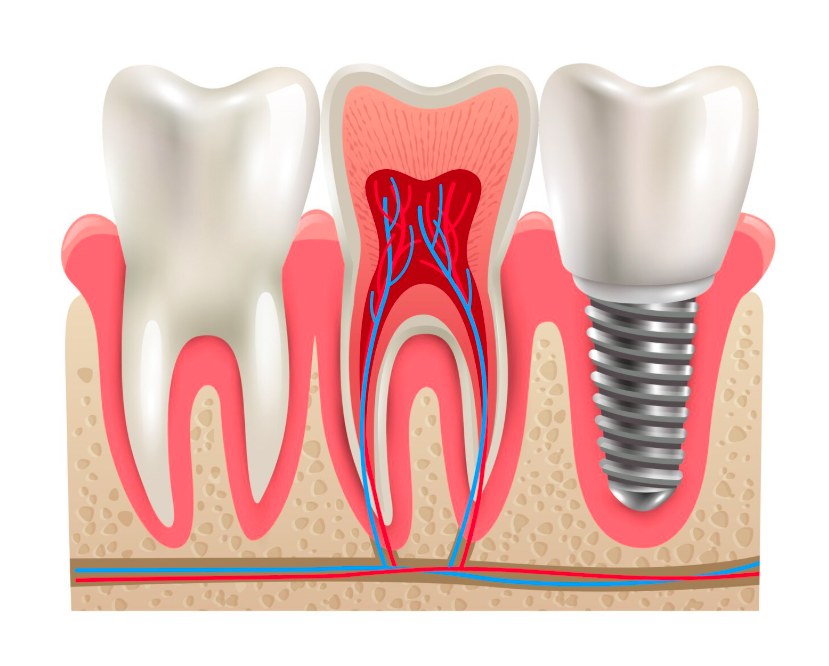

Utracony ząb to nie wyrok. Opowiem Ci, dlaczego implanty to...

Dlaczego warto uzupełniać braki zębowe? Współczesna stomatologia podkreśla znaczenie zdrowego...